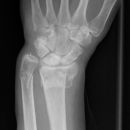

distaler Radiustrümmer Frykman VIII